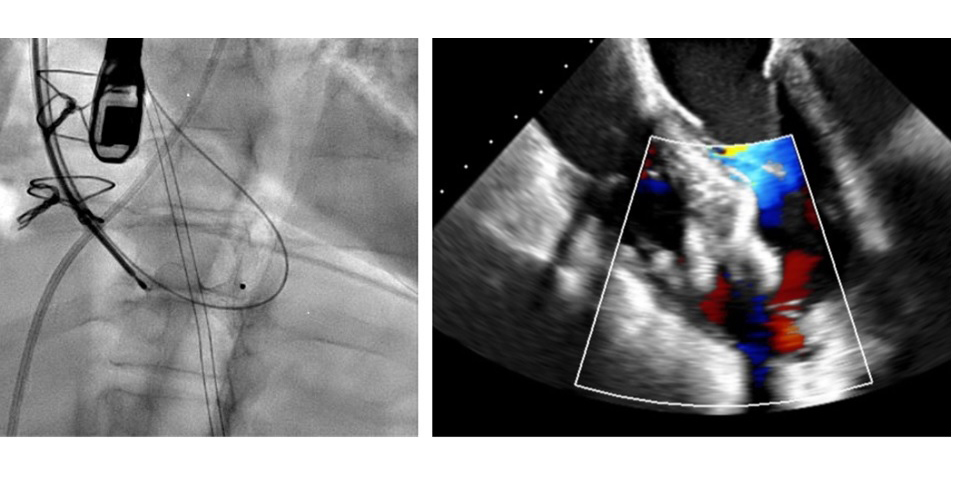

Interventional CurriculumDiagnostic technique experience includes advanced hemodynamic evaluation, intravascular ultrasound, coronary pressure wire evaluation, and optical coherence tomography, in addition to learning how to teach general cardiology fellows diagnostic cardiac catheterization. Approximately 90% of coronary angiography procedures are performed via the radial approach. The program also offers a core experience in a variety of coronary interventional techniques including percutaneous transluminal coronary angioplasty, stent implantation, cutting balloon angioplasty, venous and arterial coronary graft intervention, distal embolic protection devices, rheolytic thrombectomy, and rotational atherectomy. Interventional fellows are also trained in the use of mechanical circulatory support devices including intra-aortic balloon counterpulsation and percutaneous left ventricular assist devices as well as cardiac valvuloplasty, transcatheter closure of intracardiac communications, and pericardiocentesis.